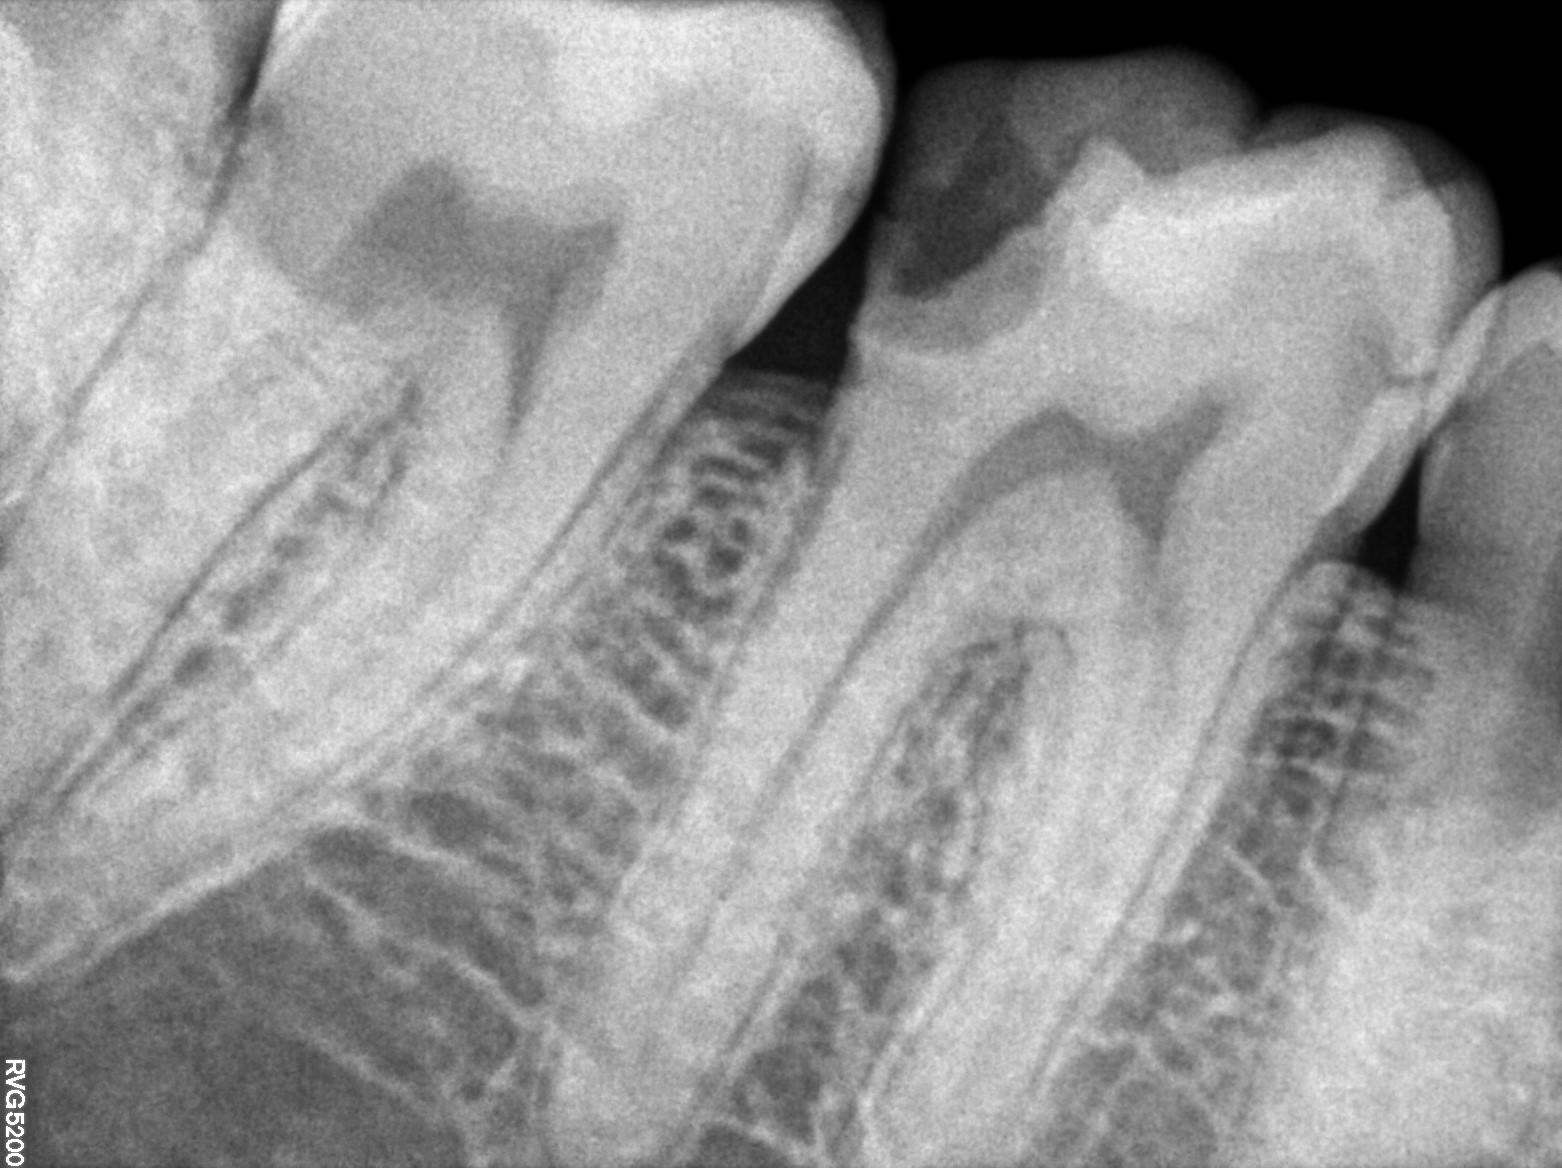

Dental Radiographs FHIR: DocumentReference · LOINC 24641-7

R5.3.jpg

24641-7